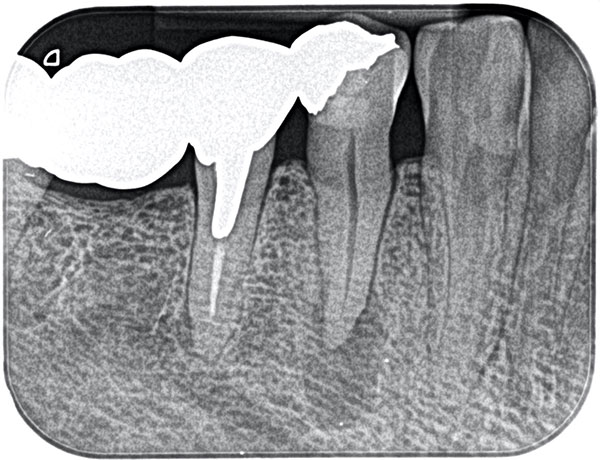

主訴: 右下がしみて痛い。

右下7根の根幹治療と親知らずの抜歯